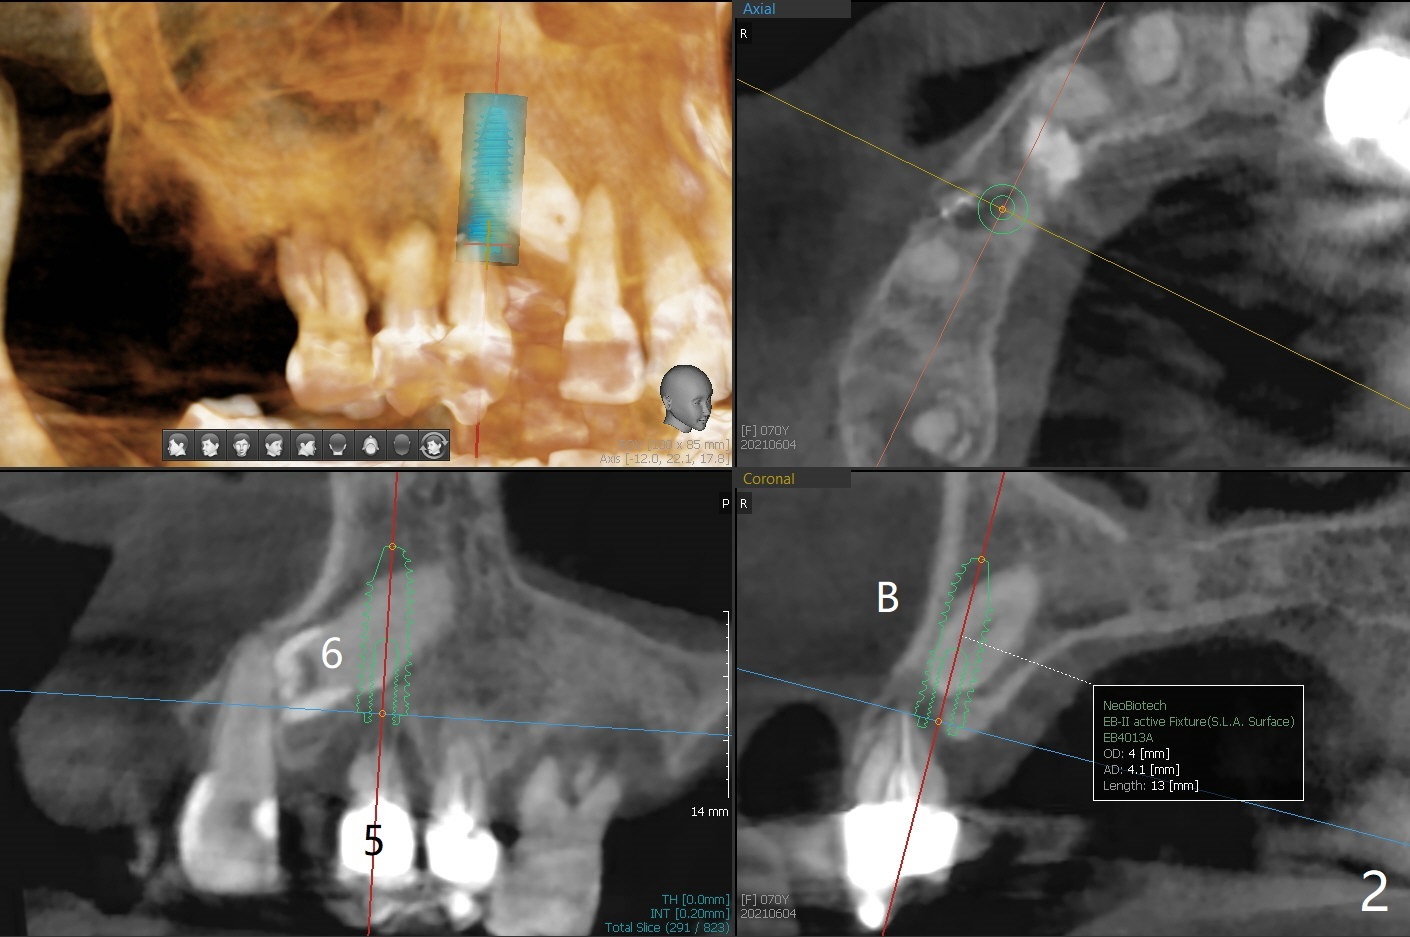

A 70-year-old woman requests implants at #3 and 5 because of bone loss (Fig.1). Since the impacted tooth #6 crosses the trajectory of the implant at #5, extraction of the former is necessary (Fig.2). Palatal bone loss is severe at #5, a 3.5x15 mm 1-piece implant will be placed slightly more buccal than what is shown for 4x13 mm 2-piece one at Fig.2. A 5x11.5 mm implant will be placed at #3 without sinus lift (Fig.3). In fact the patient is concerned about cleasenability of the cantilever bridge. One-piece implant will be placed if needed (Fig.4).